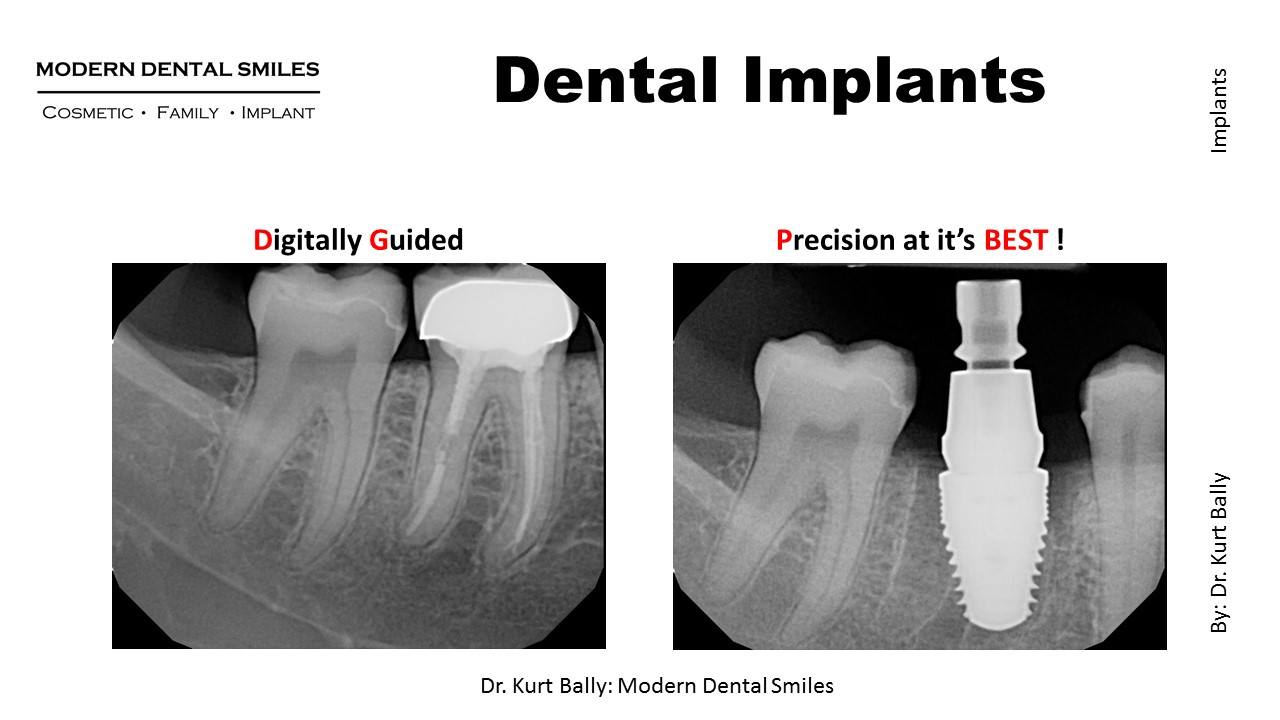

Surgical guides are important and indicated to place dental implants safety and accurately. In this case, an upper first molar was extracted, and with the aid of a Surgical Guide and Keyed Implant System, the implant was placed successfully and accurately.

Same Day Extraction, Immediate Molar Implant Placement